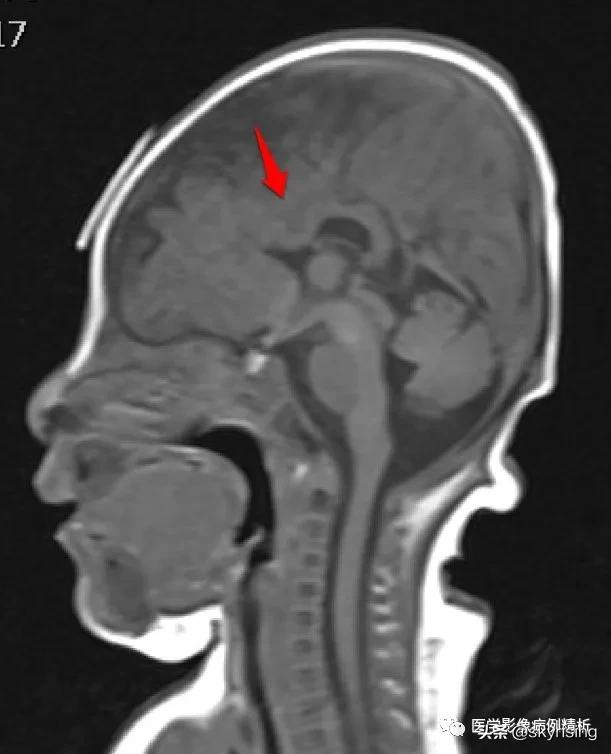

T1WI矢状位:红色箭头所示胼胝体嘴部、膝部、体前部缺如,正常扣带沟形态消失,双侧额叶延伸至侧脑室内。

MR影像表现,双侧额叶呈实质融合,大脑前纵裂缺如,后纵裂存在,胼胝体嘴部、膝部、体前部缺如,体后部及压部存在。本例即此型。